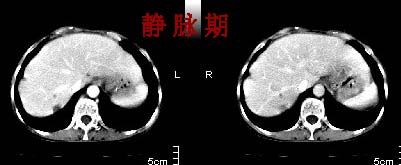

主动脉-胰腺间隙可见巨大分叶状软组织肿块影,包绕腹主动脉、腹腔干及其分支、腔静脉等大血管,增强呈无明显强化,临近脏器明显受压移位,增强示有分界。肝右叶可见局限性低密影,边缘清楚。

考虑腹膜后淋巴瘤。

肿块强化不明显(遗憾的是没有标上ct值)但胃壁强化的十分明显。